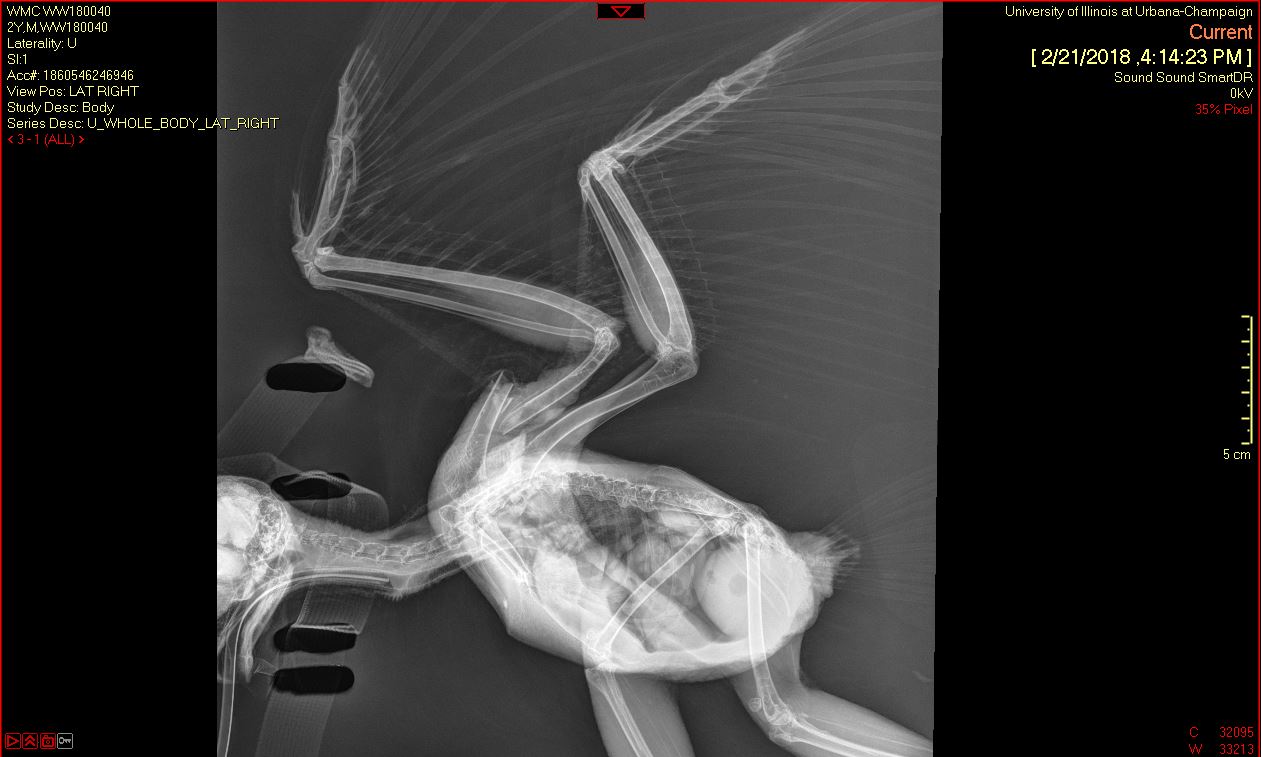

A Barred Owl was transferred to the Wildlife Medical Clinic from a nearby veterinary clinic on February 20th after being hit by a car on February 18th. In their initial exam, the team noticed an open fracture on the middle of the right humerus of the wing. Radiographs (x-rays) showed that the wing had been rotated a complete 360 degrees!

Once the wing was rotated back into normal position, the team had to wait to assess whether the portion distal to the rotation (closer to the wing tip) still had healthy blood supply. Once this was ensured, they determined the owl was a good candidate for surgery to repair the humeral fracture.

This patient recovered very well from all of these procedures! Right now, the team is planning to do PROM (passive range of motion) exercises on the wing regularly. This is an important physical therapy regimen to ensure the muscles in the the wing recover with the full range of motion that is needed for flight.